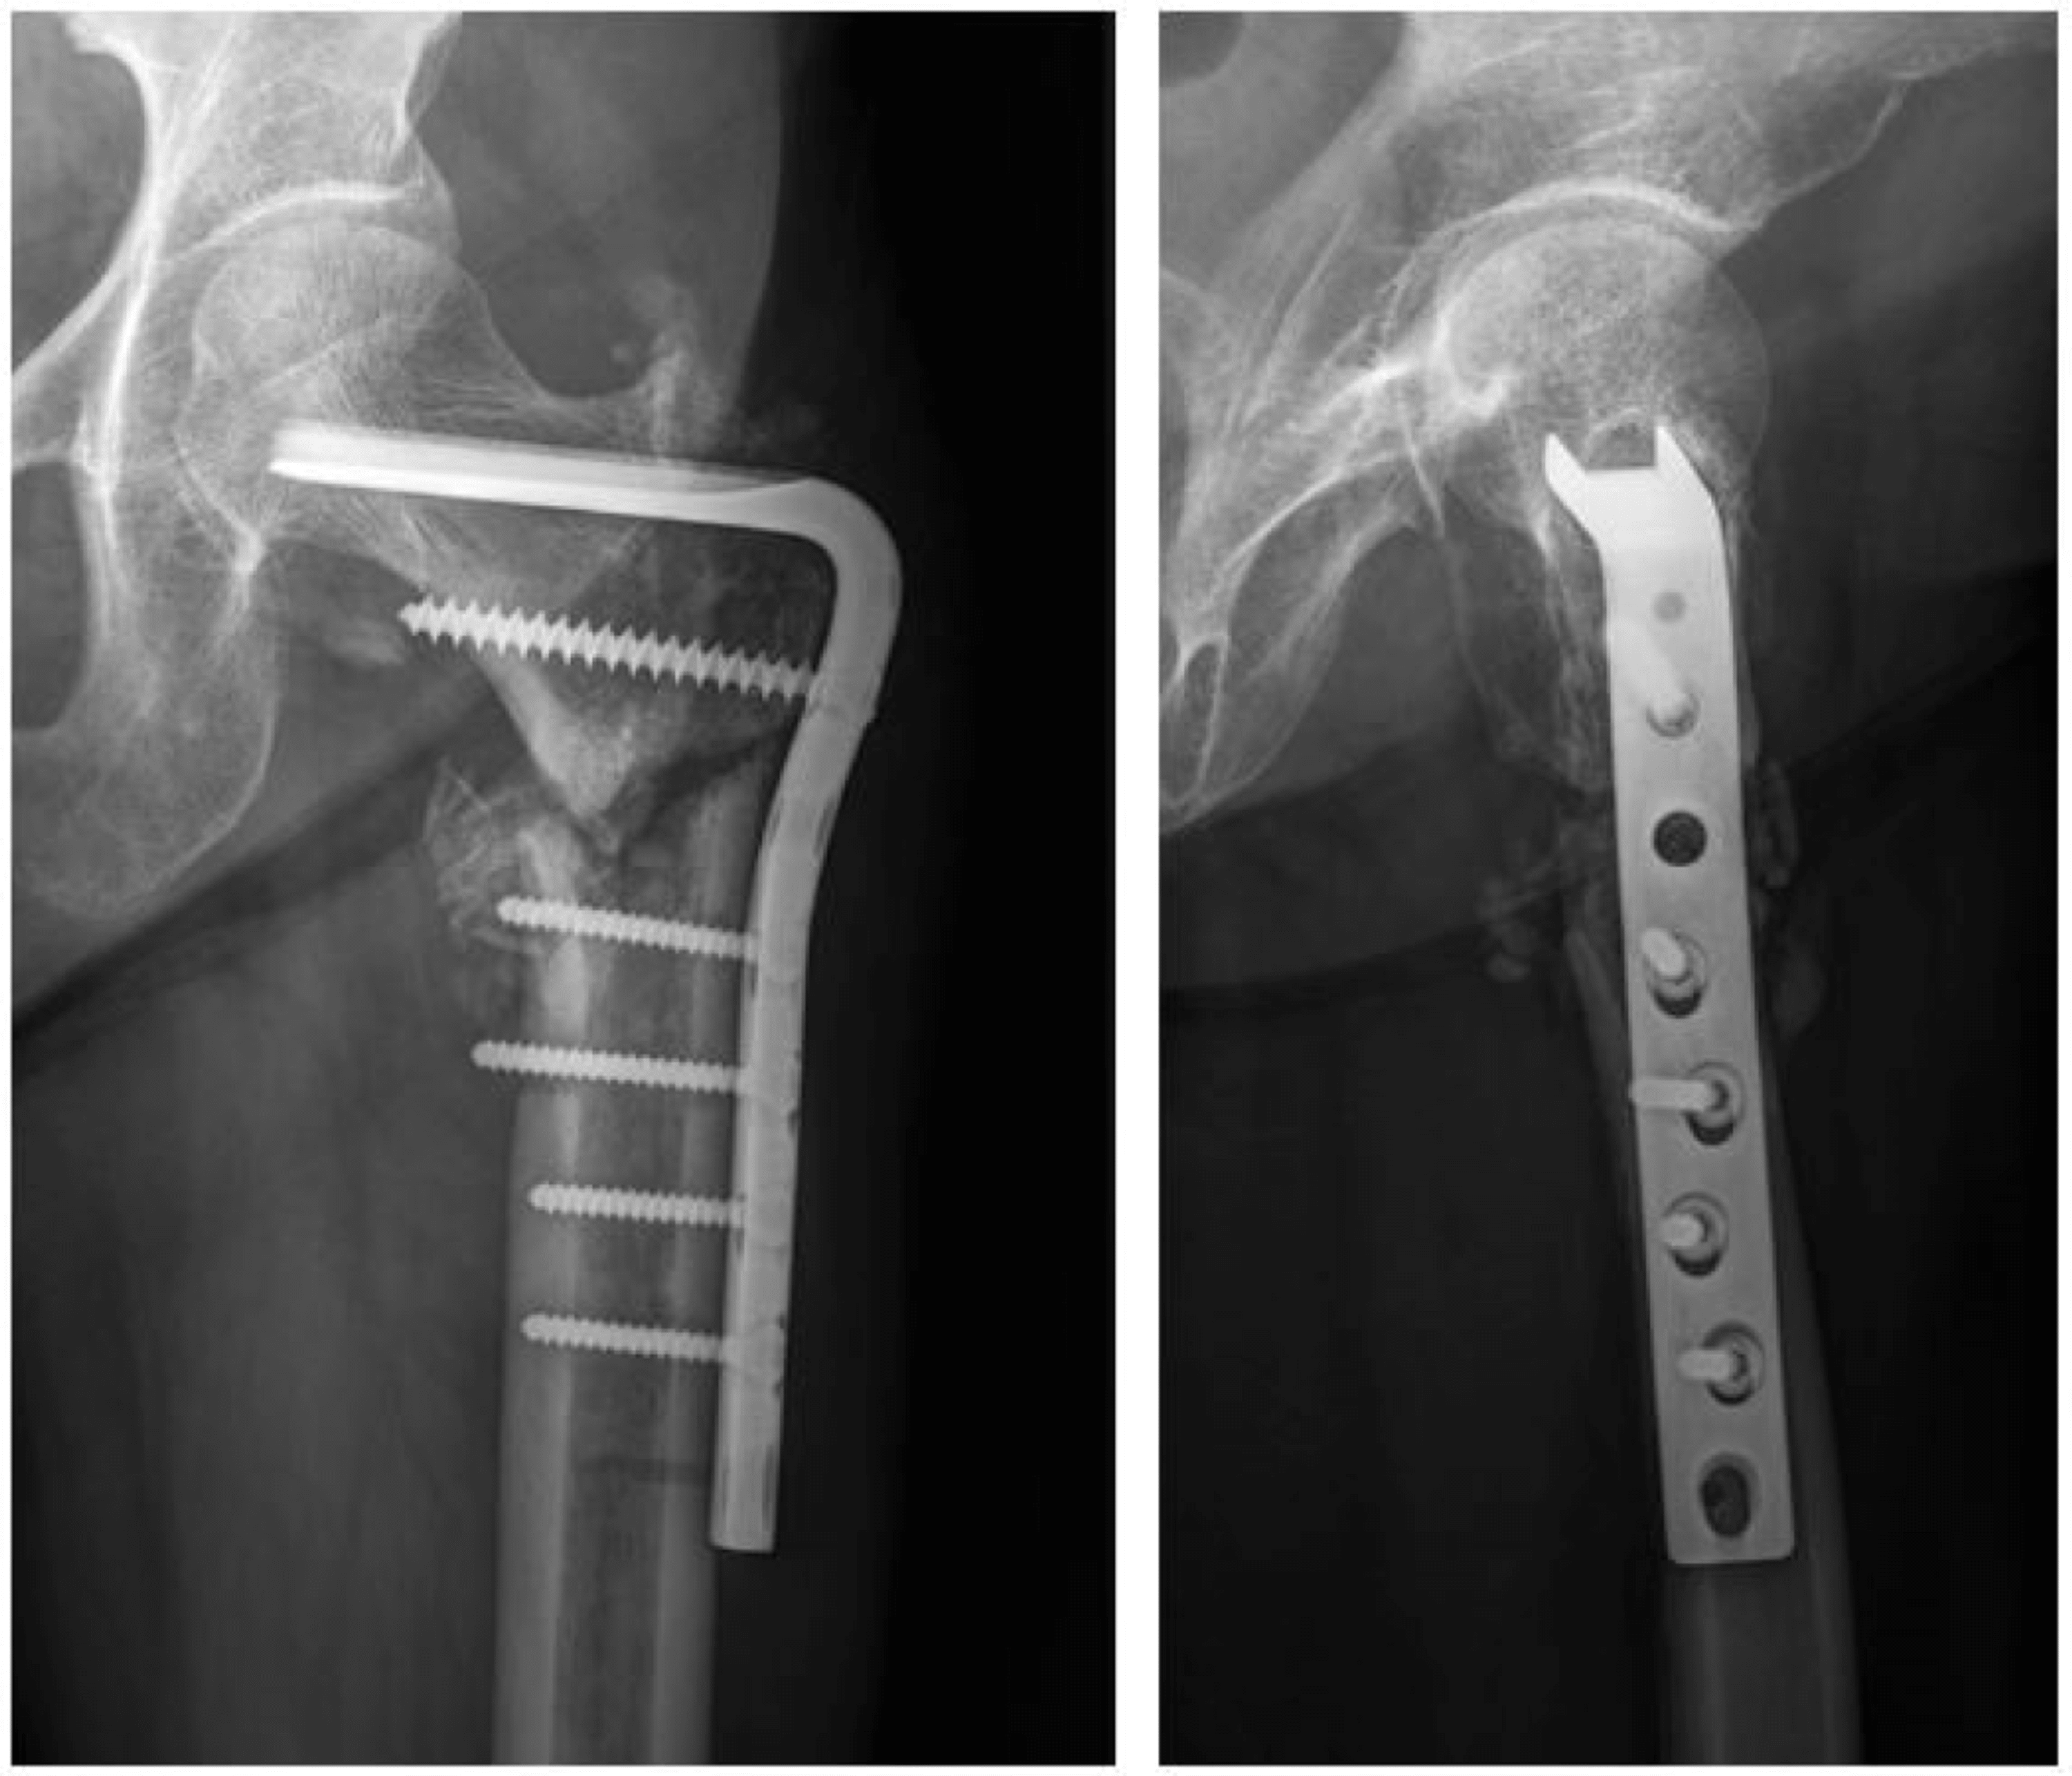

THR with femur repair at one end and bone graft at the other....after Bone Graft For Broken Femur Outline the appropriate evaluation of periprosthetic proximal. A bone graft is a choice for repairing bones almost anywhere in your body. You’ll probably have surgery 24. Bone grafting, or transplanting of bone tissue, is beneficial in fixing bones that are damaged from trauma or. bone grafting is a surgical procedure that places new bone or a replacement material into. Bone Graft For Broken Femur.

The patient underwent bone grafting and internal fixation of the distal Bone Graft For Broken Femur bone grafting is a surgical procedure that uses transplanted bone to repair and rebuild diseased or damaged bones. Identify the etiology of periprosthetic proximal femur fractures. A doctor may recommend a bone graft for many conditions, including. bone grafting is a surgical procedure that places new bone or a replacement material into spaces between or around broken. . Bone Graft For Broken Femur.

Medicina Free FullText Successful Plate Fixation with Long Bone Graft For Broken Femur You’ll probably have surgery 24. bone autografts remain the gold standard since there are no issues with histocompatibility or disease. Outline the appropriate evaluation of periprosthetic proximal. if you’ve broken your femur, your provider will do surgery so your broken bone will heal properly. Identify the etiology of periprosthetic proximal femur fractures. A bone graft is a choice. Bone Graft For Broken Femur.

Cureus Bilateral Subtrochanteric Complete Atypical Femoral Fracture Bone Graft For Broken Femur bone autografts remain the gold standard since there are no issues with histocompatibility or disease. bone grafting is a surgical procedure that uses transplanted bone to repair and rebuild diseased or damaged bones. a bone graft acts as a filler or scaffold for new bone growth. Outline the appropriate evaluation of periprosthetic proximal. Identify the etiology of. Bone Graft For Broken Femur.

(a) Atypical right subtrochanteric femur fracture created in a Bone Graft For Broken Femur Identify the etiology of periprosthetic proximal femur fractures. You’ll probably have surgery 24. Bone grafting, or transplanting of bone tissue, is beneficial in fixing bones that are damaged from trauma or. a bone graft is a surgical procedure used to fix problems with bones or joints. A doctor may recommend a bone graft for many conditions, including. bone. Bone Graft For Broken Femur.

Impaction bone grafting for femoral revision hip arthroplasty with Bone Graft For Broken Femur a bone graft is a surgical procedure used to fix problems with bones or joints. bone autografts remain the gold standard since there are no issues with histocompatibility or disease. bone grafting is a surgical procedure that uses transplanted bone to repair and rebuild diseased or damaged bones. a bone graft acts as a filler or. Bone Graft For Broken Femur.